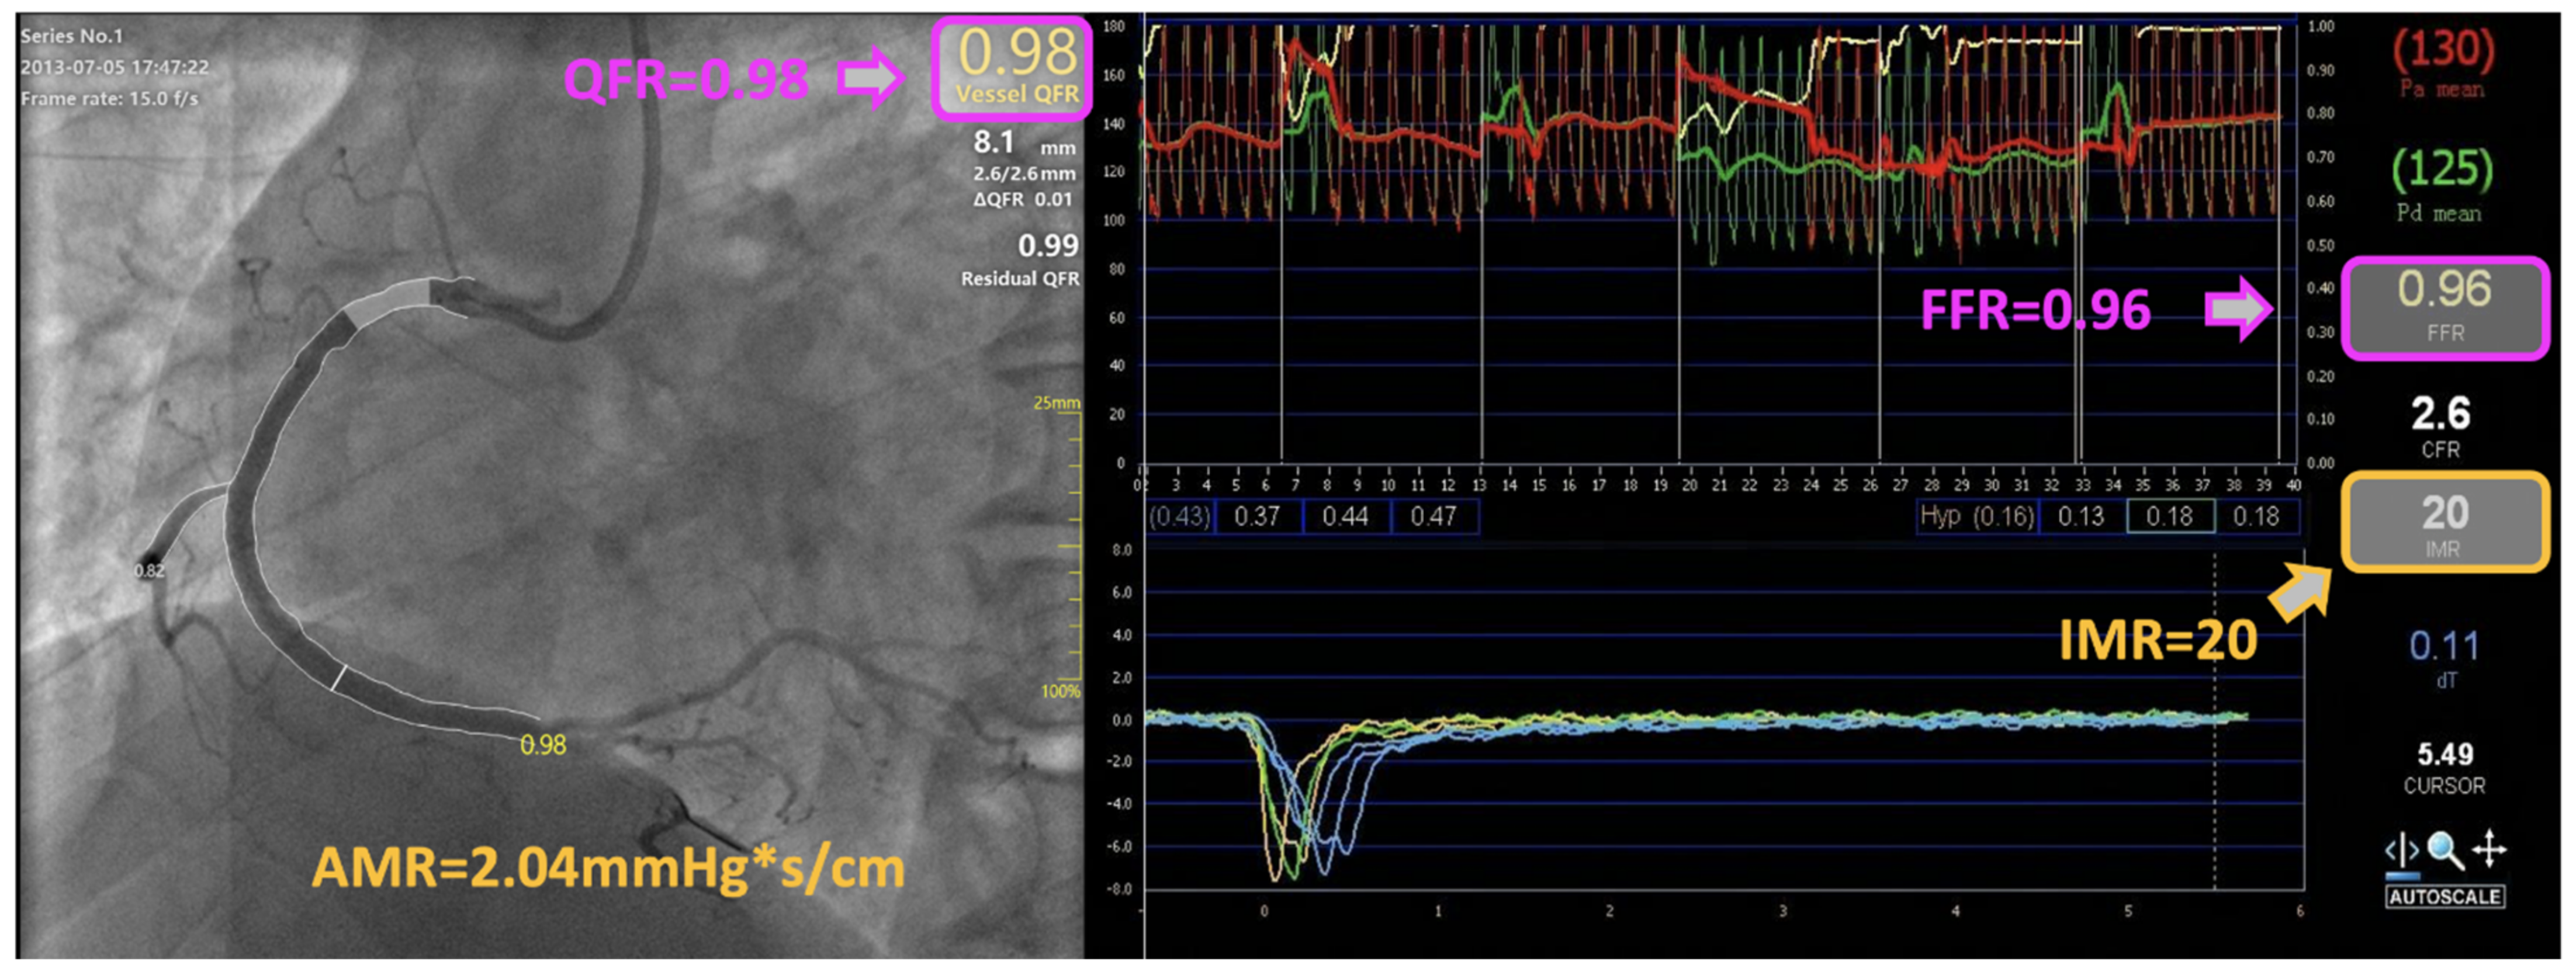

| FFR | 0.91 (0.87, 0.96) |

| QFR | 0.94 (0.91, 0.97) |

| IMR | 23.6 ± 6.8 |

| AMR, mmHg*s/cm | 2.5 ± 0.5 |